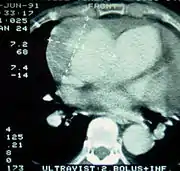

تصوير الأوعية الدموية بالأشعة المقطعية بالكمبيوتر

![]() |

| الأشعة المقطعية بالكمبيوتر (CT) | الصورة الرمزية |

| تسلخ الأبهر لحالة تنتمي للمجموعة A في تصنيف Stanford 1 الأبهر الصاعد، التجويف الشرياني الأصلي - 2 التجويف الشرياني الكاذب - 3 الشريان الرئوي 4 الأبهر الهابط - 5 فقرة صدرية | |

يعد تصوير الأوعية الدموية بالأشعة المقطعية بالكمبيوتر من الاختبارات السريعة غير الجراحية التي من شأنها توفير صورة دقيقة ثلاثية الأبعاد للأبهر. يتم التقاط هذه الصور عن طريق أخذ صور مجزأة رقيقة وسريعة للصدر والبطن، والجمع بينها باستخدام الكمبيوتر لتكوين شرائح مستعرضة. لتصوير الأبهر بالدقة اللازمة للوصول إلى التشخيص السليم، يتم حقن مادة تباين معالجة باليود في أحد الأوردة المحيطية (الطرفية). تُحقن مادة التباين وتُجرى الأشعة باستخدام تقنية تتبع الدفقة (Bolus Tracking method). يعد هذا نوعًا من الأشعة المتزامنة مع الحقن بهدف التقاط صورة مادة التباين حال دخولها إلى الشريان الأبهر. ستقوم الأشعة بعدئذ بتتبع مادة التباين أثناء تدفقها عبر الوعاء الدموي.

تتراوح نسبة خاصية الحساسية لهذه الأشعة ما بين %96 و%100، وتتراوح نسبة خاصية النوعية ما بين %96 و%100. من ضمن عيوب هذه الأشعة ضرورة توفر مادة تباين معالجة باليود إضافةً إلى عدم القدرة على تحديد موقع الجزء المتمزق من البطانة الداخلية للشريان.